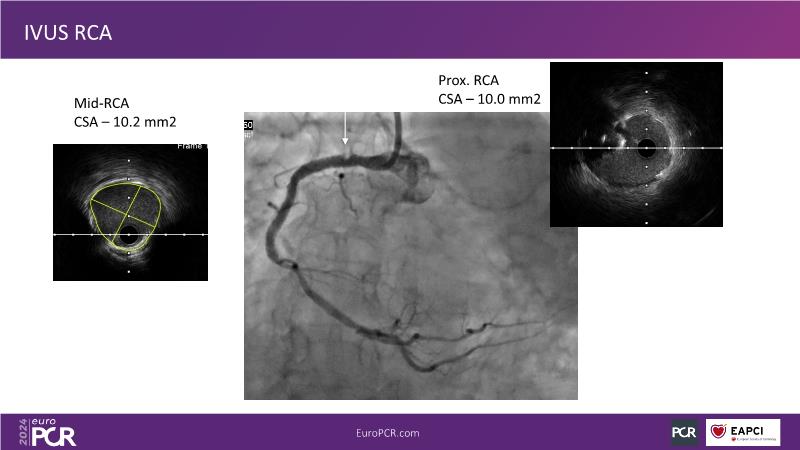

From innovation to reality: the impact of Cre8 EVO technology on complex PCI

Sponsored by Alvimedica